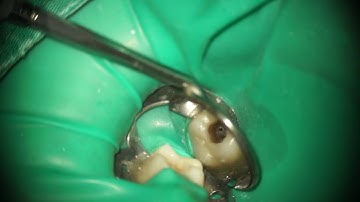

Glide Path Management - Working Length & Patency